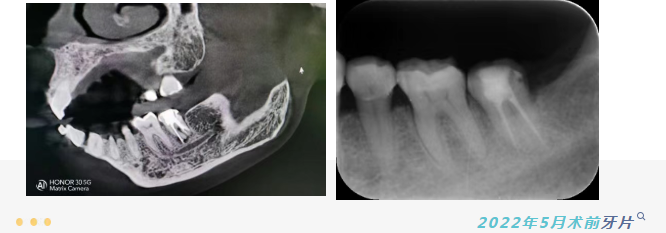

郑女士辗转来到我院,经过蒋士勇医生检查,发现情况远比想象中复杂:患牙不仅存在根管治疗不完善、根尖区已有暗影,更棘手的是,牙齿内部发生了“侧穿”(即根管侧壁被意外穿通),且填充材料超出根尖近4毫米。这些复杂的失败情况,使得常规的根管再治疗难以施行,按照传统方案,拔除患牙几乎是唯一选择。